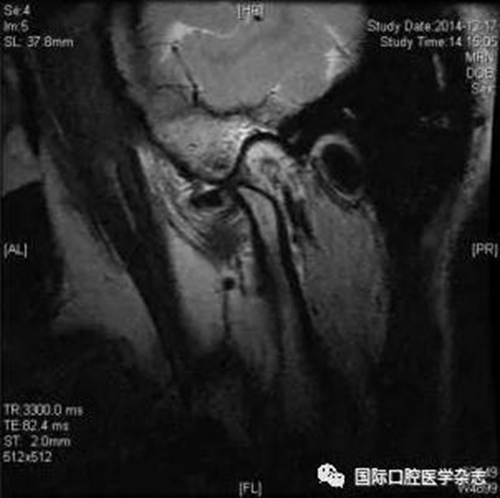

(2)不可復性關節(jié)盤前移位(圖1):多見于青壯年,往往與社會心理因素、牙合關系異常、代謝因素、偏側咀嚼、夜磨牙及不良習慣等因素相關。張口運動時,受髁突擠壓變形的關節(jié)盤不能復位;臨床有典型的關節(jié)彈響病史,進而彈響消失,出現(xiàn)開口受限,開口時下頜偏患側及關節(jié)區(qū)疼痛。測量被動開口度時,開口度不能增大。輔助檢查中,錐形束CT顯示關節(jié)前間隙增寬,造影片或核磁共振成像(magnetic resonance imaging,MRI)顯示不可復性關節(jié)盤前移位。

圖 1 不可復性關節(jié)盤前移位